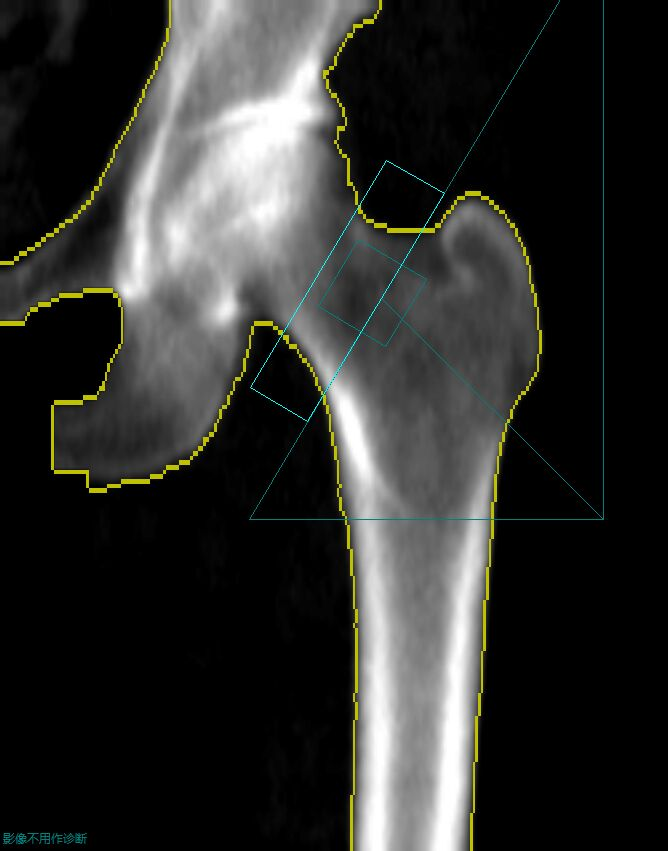

现代社会中,骨骼疾病特别是骨质疏松等骨代谢性疾病发生率日渐上升。为加强对骨代谢疾病的临床基础研究,我院引进GE LUNAR是GE医疗推出的骨密度检测设备系列,主要采用双能X线吸收法(DXA)技术,用于骨质疏松症的诊断和骨密度评估。其代表型号如Prodigy、iDXA等,核心优势在于辐射剂量极低(仅为胸片的1/100)、检测精度高,支持全身骨密度测量及肌肉脂肪分析,广泛应用于绝经后妇女、老年男性等骨质疏松高危人群的筛查与随访。

GE LUNAR的Prodigy和iDXA作为双能数字化X线骨密度测量的尖端设备,检测准确性较高,其测量精准,是精度记录的保持者(精度达0.6%),且唯一采用中华医学会建立的中国大陆人骨密度参考数据库,有助于更准确的诊断。